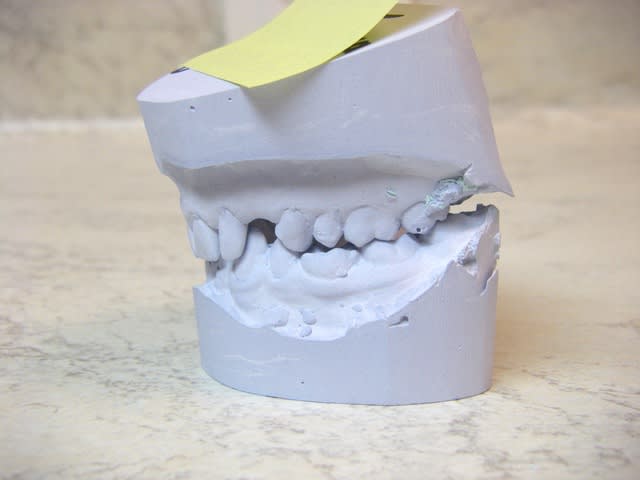

bon, photos des moulages...vites fait avec un petit apn...la flemme de sortir le reflex...;-)

pour seespan, les moulages sont trompeurs dans le volume dispo...cette patiente est un modèle miniature au niveau du volume des maxillaires et des dents!!!